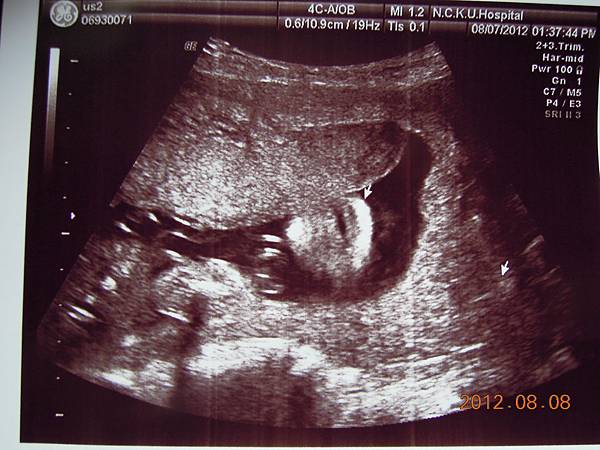

女醫師看起來超熟練,一邊照還會邊跟我解釋,這是逼逼的大腿,小腿,心臟,腎臟.....等等器官,一邊跟我媽聊天,說他生幾個....

除了比較明顯的骨頭可以看的出來,其實我們看不太懂,但是他精熟的技術很快把每個部位的大小都量測出來,我躺在床上看著上頭的螢幕,慢慢欣賞他的每張超音波照片~~

可以看到的是在逼逼的上方剛好被胎盤擋著,比較看不到他的正面,除了肛門無法看到(怕沒有肛門),醫師說現在看不到,小雞雞也沒照他的大小(我怕他發育不良),其他身體器官包括腦部剖有量測他的大小及羊水多寡(我怕像上次一樣羊水太少),今天量出來是12,喔彌陀佛~~

大約檢查了有四五十分鐘,也數了他的手指腳趾,看起來是沒異狀,就叫我等下把報告拿過去門診給游醫師看,還給我ㄧ堆照片,就是下面那些~~

接下來就是他的一堆檢查照片啦~~